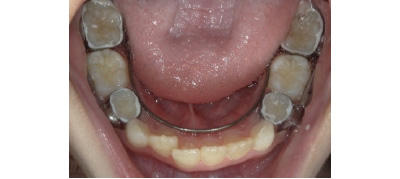

痛みの感じ方には個人差がありますが、多少はあると思っていただいた方が良いかと思います。小学生頃に行う第1期治療は、上下のアゴを広げて永久歯のスペースを作ります。こちらの装置は、痛みよりは食べにくい・喋りにくいなどの違和感の方がある方が多いです。

奥歯には金属のバンドが入りますので、噛んだ時に多少違和感や痛みを感じる方もいます。しかし、1週間ほど様子みていたけると徐々に慣れていきます。

その後、前歯にワイヤーが付くと歯を少しずつ動かしていくのでワイヤー調整後2~3日はズーンとするような痛みを感じる方もいます。